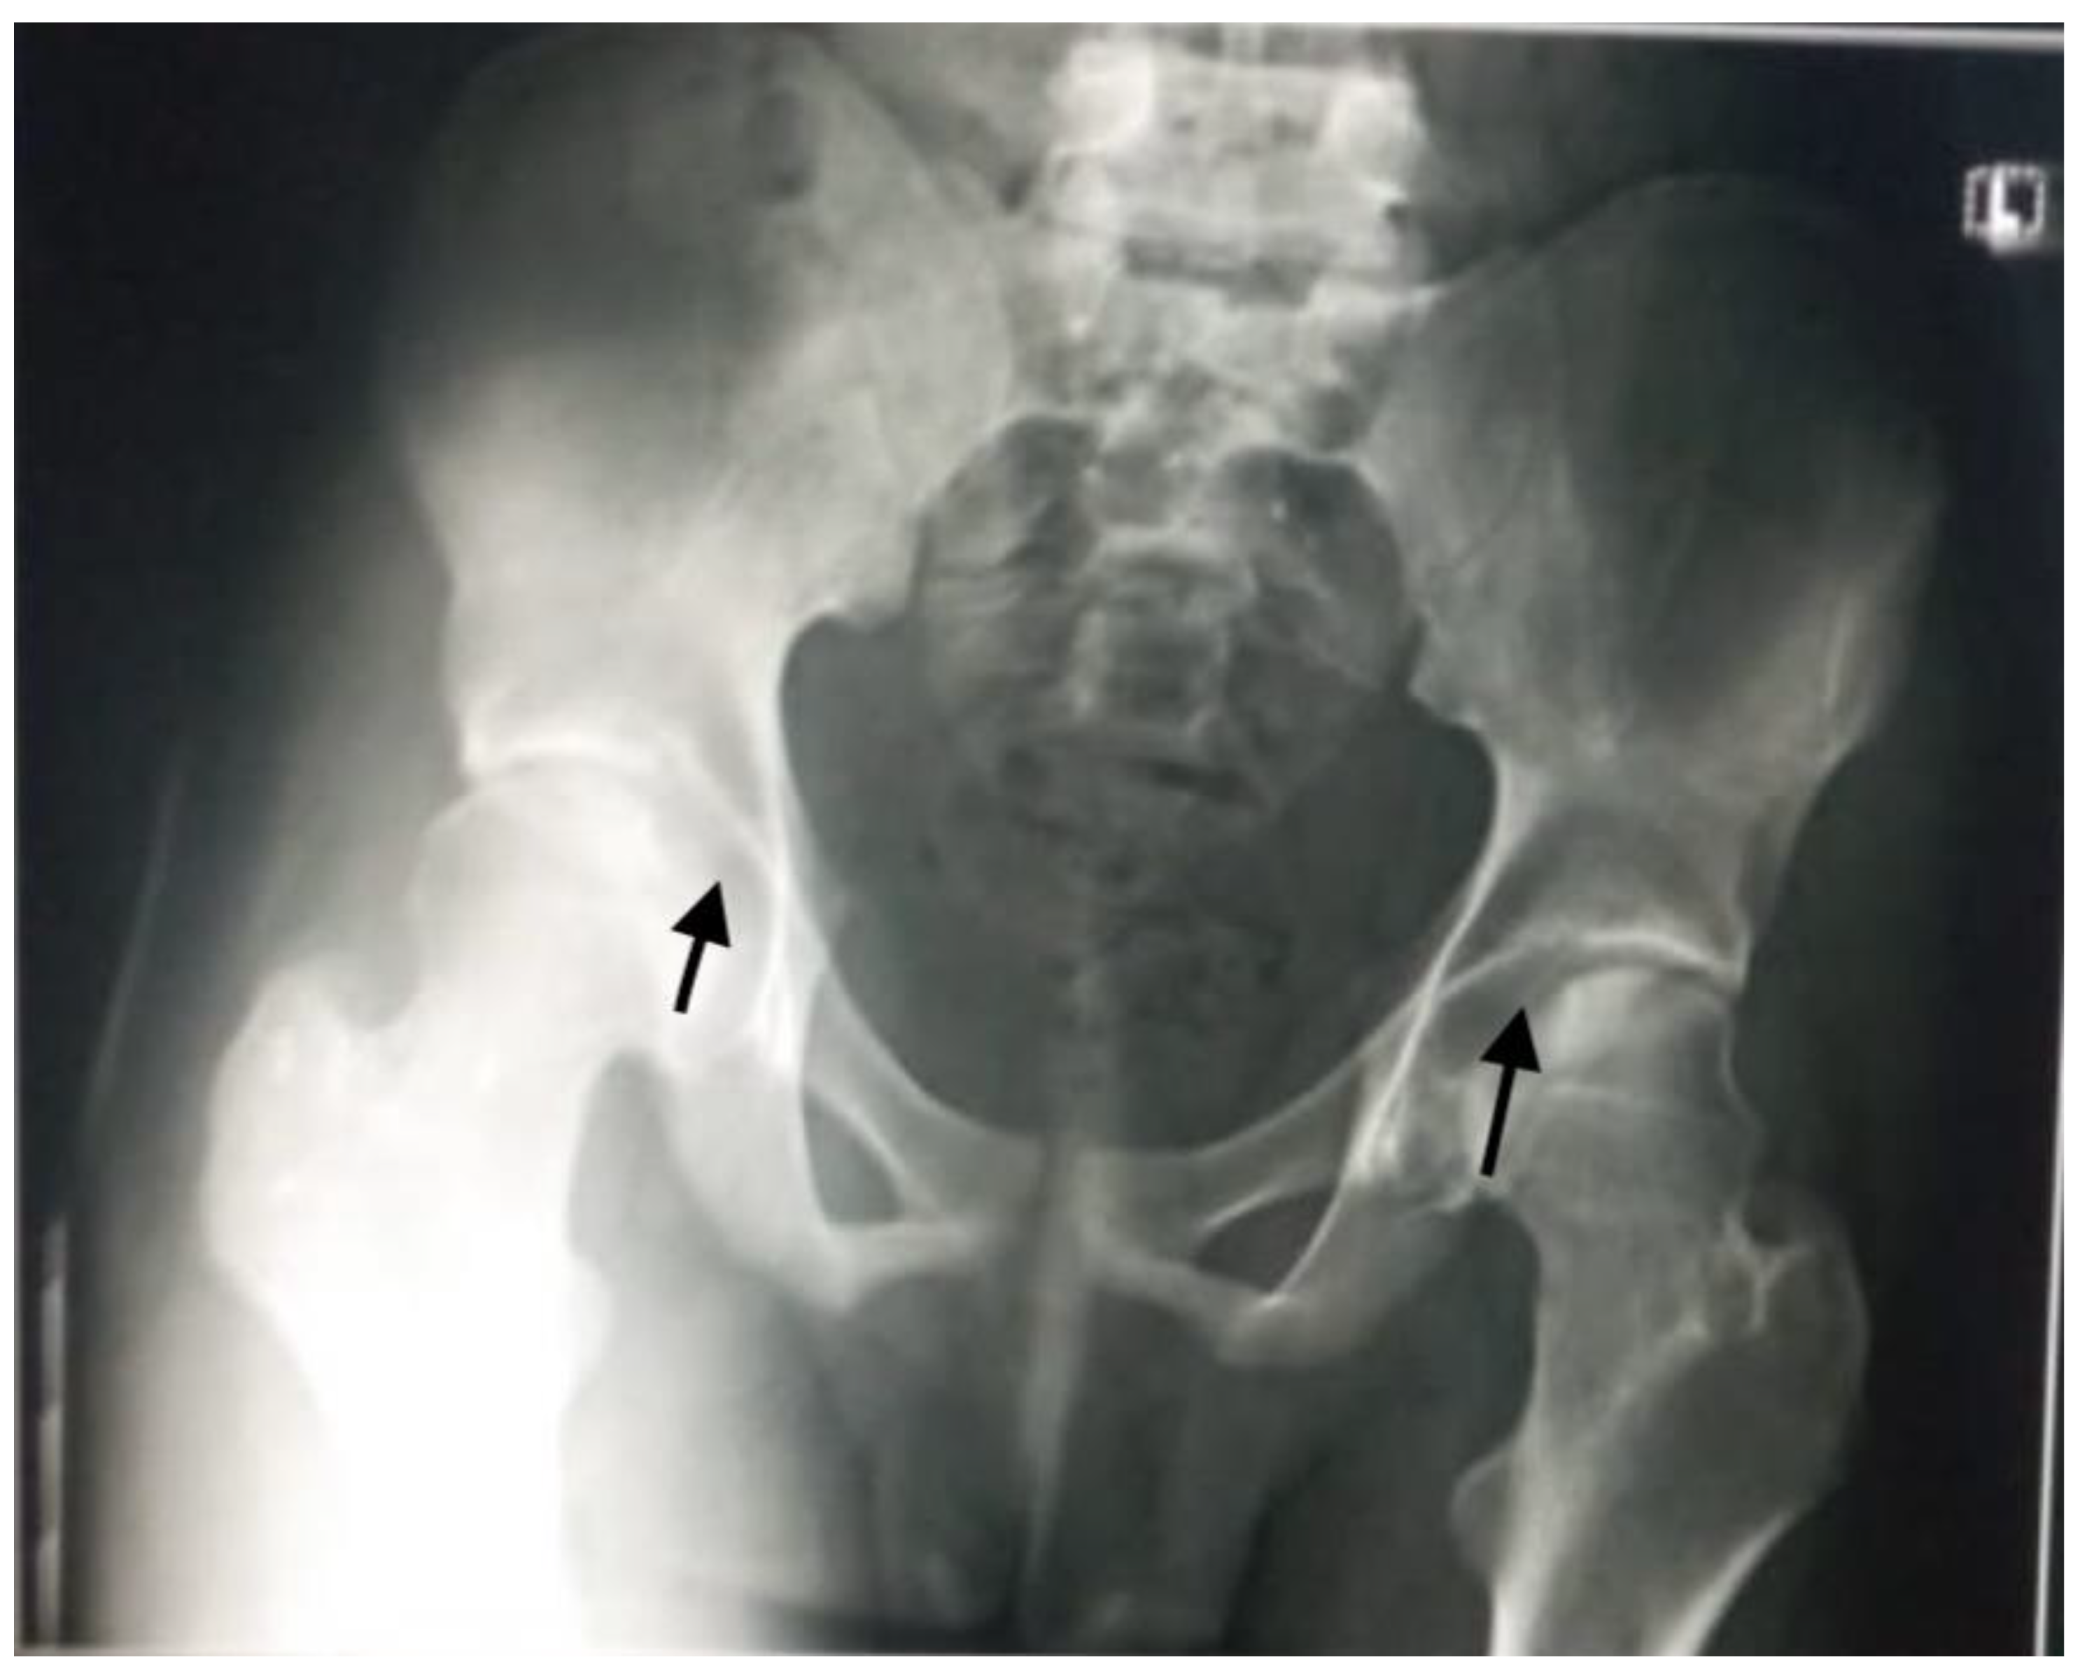

Aseptic necrosis of the femoral head is also a common complication of fractures in adolescents with sickle cell anemia as evident in our patient in Figure 5. Another common bone involvement in sickle cell disease patient is osteonecrosis. Osteonecrosis in sickle cell patients tends to affect a larger bone surface area than osteonecrosis due to other etiologies [18]. According to several works of literature, the increased risk of osteonecrosis of the femoral head in our patient group could be linked to an overall reduction in bone mineral density and marrow hyperplasia compared to the general population [18,19].

Figure 5. Plain radiograph showing avascular necrosis of the bilateral femoral head (black arrows). Commonly seen in sickle cell disease patients due to poor blood circulation from the disease condition.